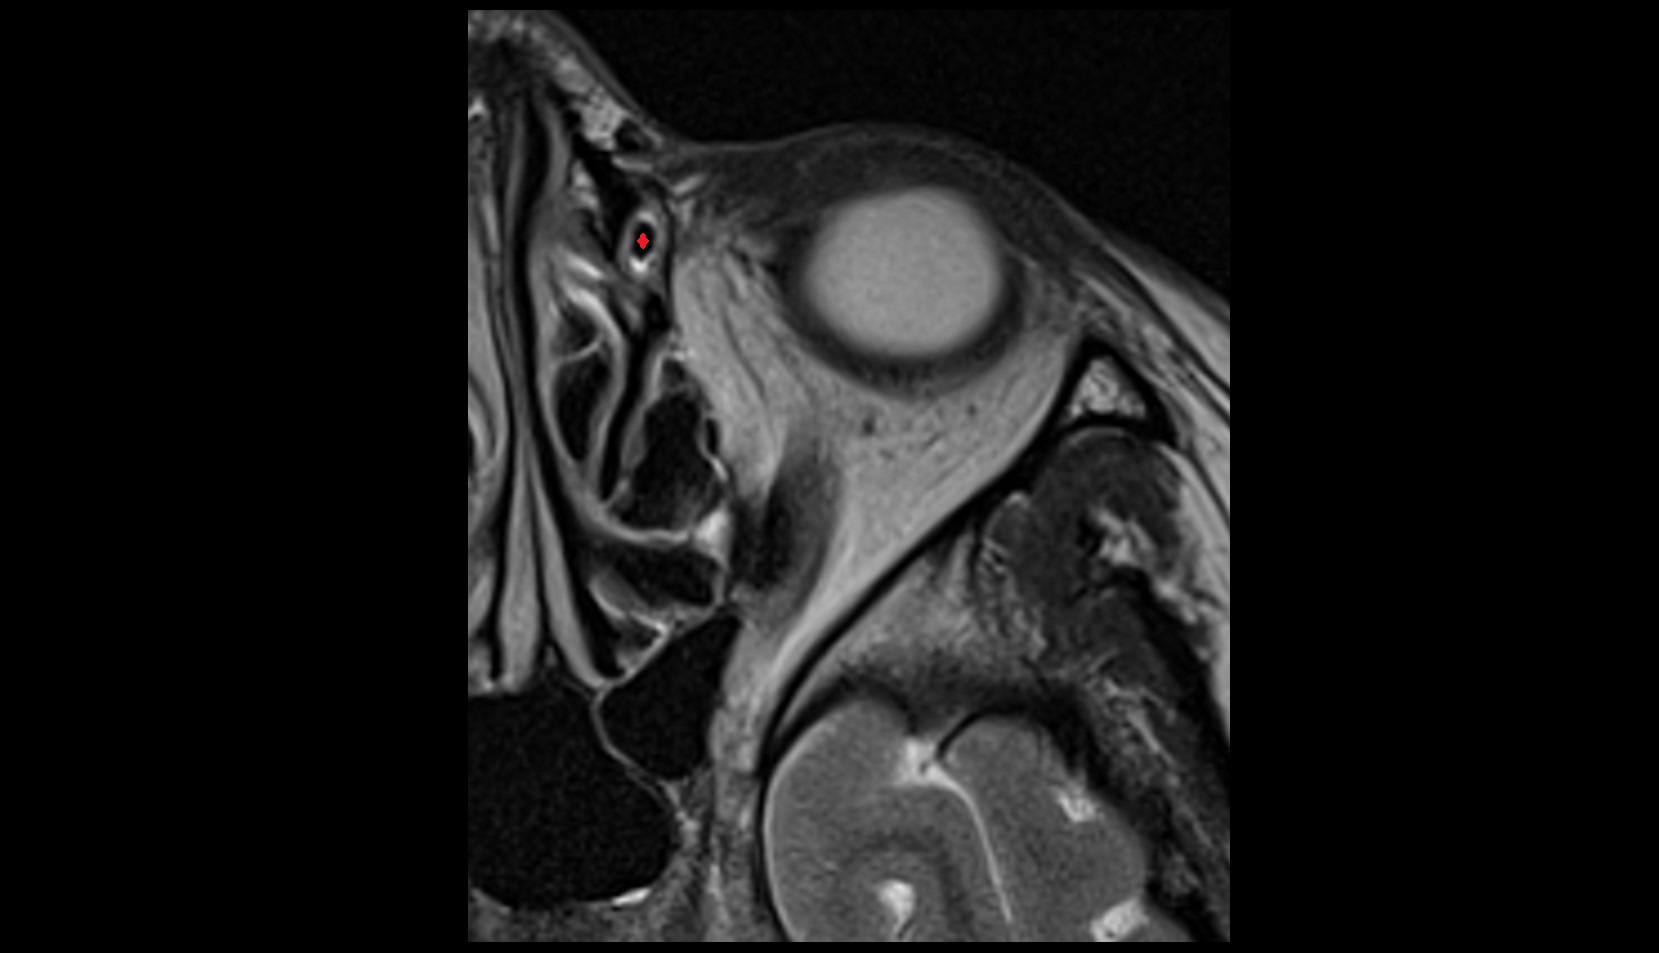

- Uterus

- Body of uterus

- Fundus of uterus

- Cervix of uterus

- Isthmus of uterus

- Vagina

- Ovaries

- Right ovary

- Left ovary

- Fallopian tube

- Suspensory ligament of ovary

- Broad ligament of uterus